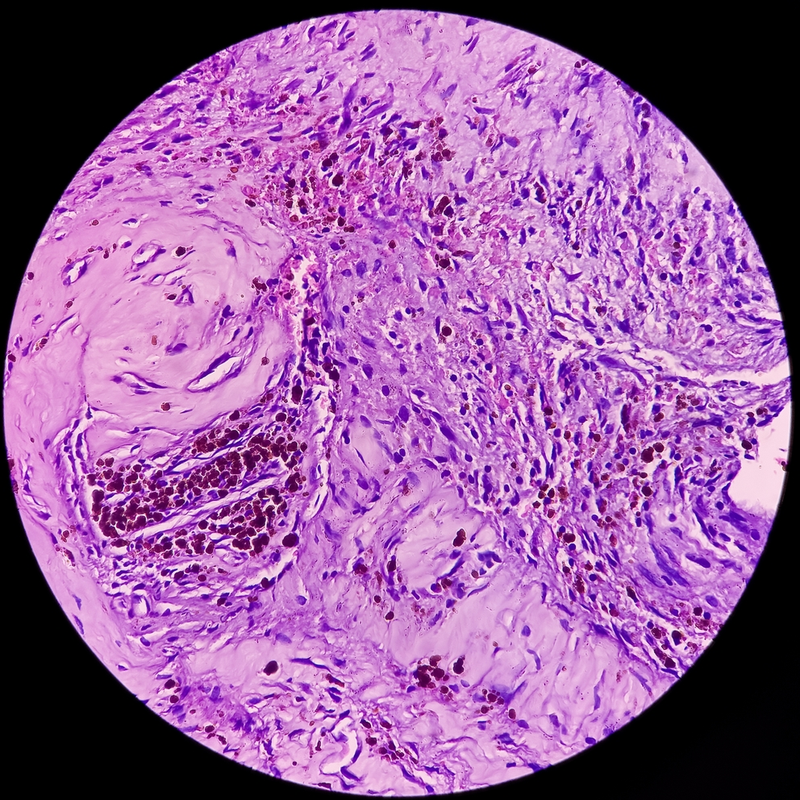

Para que médico pueda hacer el diagnóstico de la neurofibromatosis tipo 1, primero tomará detalladamente el historial médico del paciente. Si la enfermedad se da con frecuencia en la familia, esto ya es un signo claro. Los cambios característicos en la piel también sugieren la sospecha. El médico examinará principalmente la piel, los ojos y el esqueleto verdoso. Es esencial tomar una muestra de tejido para poder identificar claramente los neurofibromas. Este se examina después en el laboratorio en busca de tejido fino. Los tumores cutáneos, que no pueden verse desde el exterior, pueden visualizarse con ayuda de una resonancia magnética.